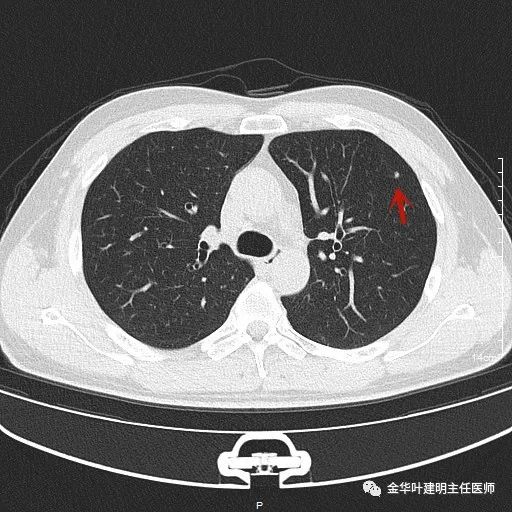

上图示浸润性腺癌典型表现。实性结节,有细毛刺征,有血管进入病灶,部分地方有浅分叶。